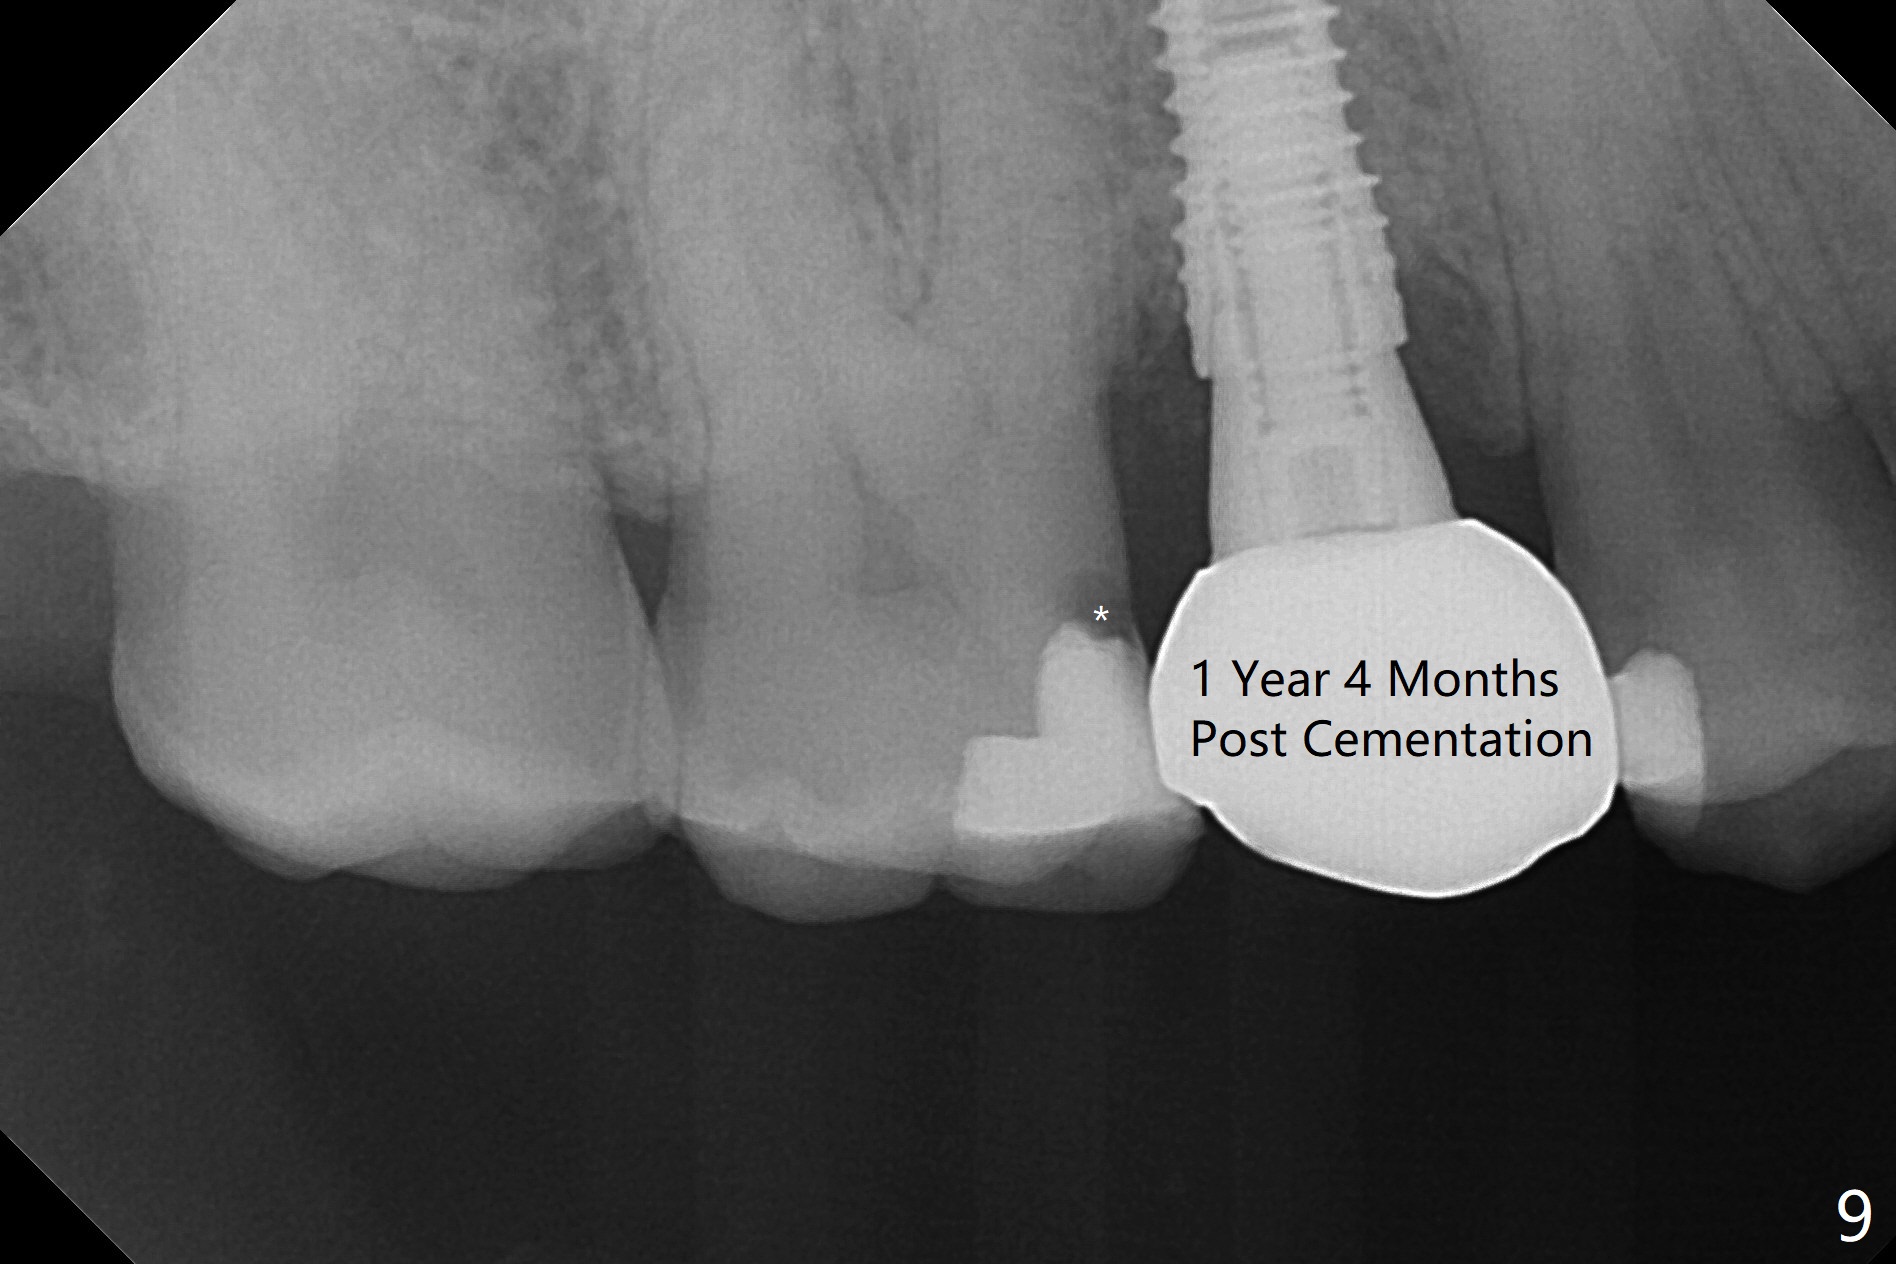

When the tooth #4 with vertical root fracture (Fig.1) is extracted, the buccal plate is found to be lost. The lowest point of the defect is shown as black dashed line in Fig.2 (yellow dashed line: sinus floor). After use of 2.5 mm reamer for 21 mm (buccal gingival level) and 3.0 mm reamer for ~17 mm, a 3.8x15 mm dummy implant is placed with 30 Ncm and 1.85 mm apical space (Fig.3 pink outline). A 3.8x18 mm (definitive) implant is placed with <40 Ncm with the implant plateau apical to the lingual crest (Fig.4,5). The buccal plate defect is repaired by Vanilla Graft (Fig.6 *) before and after insertion of a 4.5x4(3) mm abutment. The buccal plate defect seems to being repaired 4 months postop (Fig.7). Occlusal wear suggests bruxism, which is also associated with the root fracture. Night guard is recommended. The defect repair is close to completion 8 months post cementation (Fig.8). The crown/abutment is found to be loose 1 year 4 months post cementation and retightened without checking whether there is clinical 2nd DO caries of #3 (Fig.9, "sensitive to water pik"). A few days later, DO composite is being removed. It is difficult to determine whether the 2nd DO caries or gap has been removed with the neighboring crown in place. When the crown/abutment is removed and gingival retractions are inserted, there is no decay. The gap is removed. With Toflemire in place, the crown/abutment is reseated and hand tightened; after packable composite, the crown/abutment is removed, there is no more DO gap.

In fact there is a small buccal fistula, which is communicated with the underlying implant threads. Although preop CT shows that the buccal crest is lower than the palatal (3.8x13 mm, Fig.10 P) one, intraop finding of missing buccal plate should dictate a shorter implant (Fig.11) or onlay graft to avoid periimplantitis. Regeneration of the bone plate is limited. Later the fistula disappears with formation of a concavity (Fig.13). There is no symptom. Is bone graft necessary with a remote incision? 3-D images of CT taken 1 year 5 months post cementation show possible mesiobuccal and distopalatal bony defects (Fig.13-16). It is possible that bone graft was placed enough palatal (Fig.16). DO composite at #3 is redo satisfactorily (Fig.17 *).